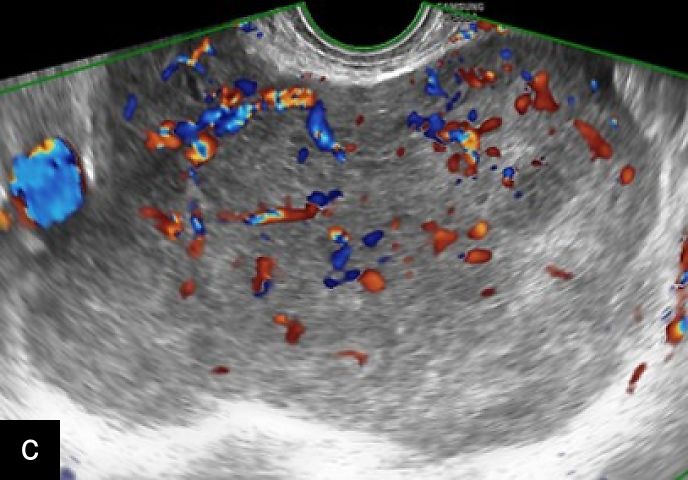

3

Transvaginal (a) and transabdominal (b) ultrasound images of uterine sarcoma. The lesion exhibits heterogeneous echotexture, irregular margins and peripheral vascularity on color Doppler. While uterine sarcomas are often highly vascularized, cases with lower vascularization can pose challenges in the differential diagnosis from benign myometrial lesions, such as atypical leiomyomas.